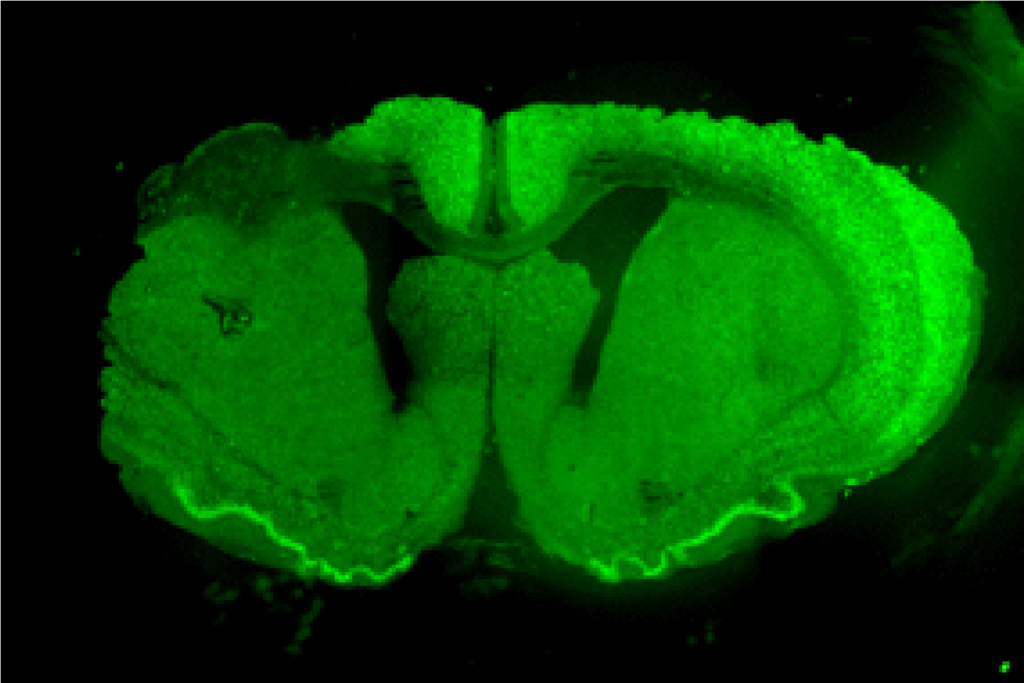

脳や脊髄の病気に対する骨髄間質細胞再生治療の開発

脳や脊髄の病気では、しばしば重篤な後遺症が生じます。 たくさんの新規治療法が開発されつつありますが、 中枢神経系では再生能力が限定的であるため、その治療効果は不十分です。 近年、再生医療研究が急速に進歩しており、中枢神経疾患に対する骨髄間質細胞移植治療が期待されています。 我々は脳梗塞・脳出血・脊髄損傷・認知症などの動物モデルを用いて、 幹細胞・幹細胞足場材複合体・幹細胞分泌物(エクソソーム)などを用いて、 機能回復が得られないかどうかの研究を進めています。また研究の実用化に向けて、 自動培養装置の開発や知的財産権(特許)の取得などにも着手しております。